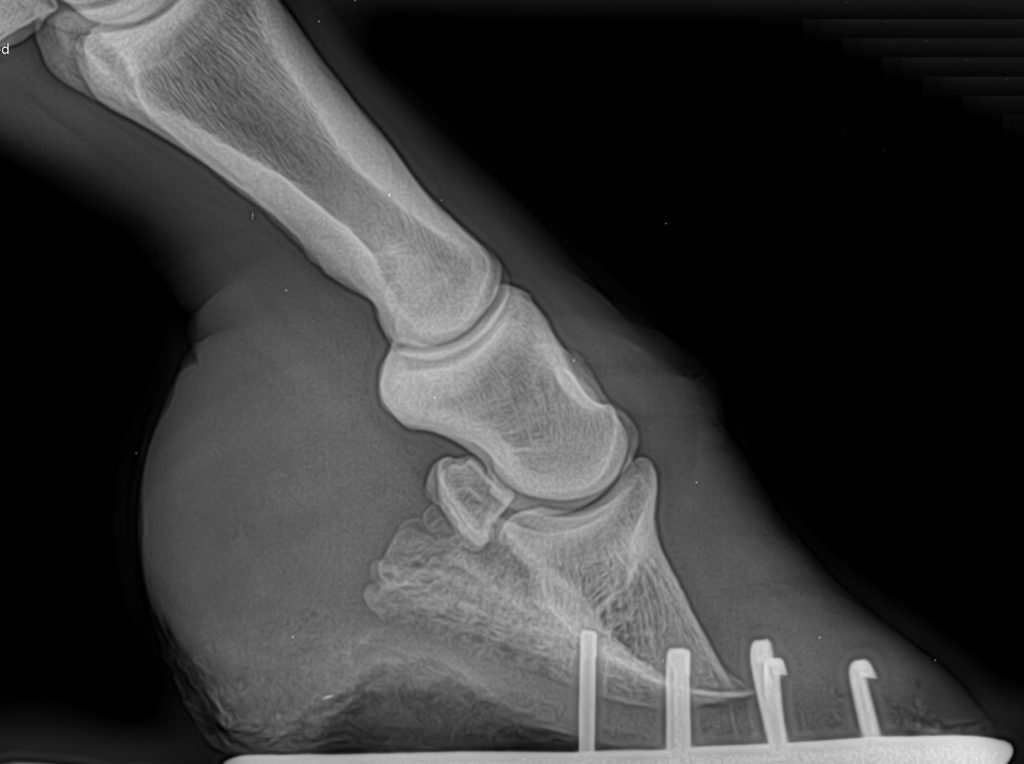

L’imagerie : des radios des pieds sont faites, on place un clou en guise de repère sur la paroi en pince. On regarde ensuite l’inclinaison de la troisième phalange. La paroi et la phalange doivent êtres parallèles. On peut ainsi déterminer le degré de basculement et de rotation de la phalange (ou son absence).